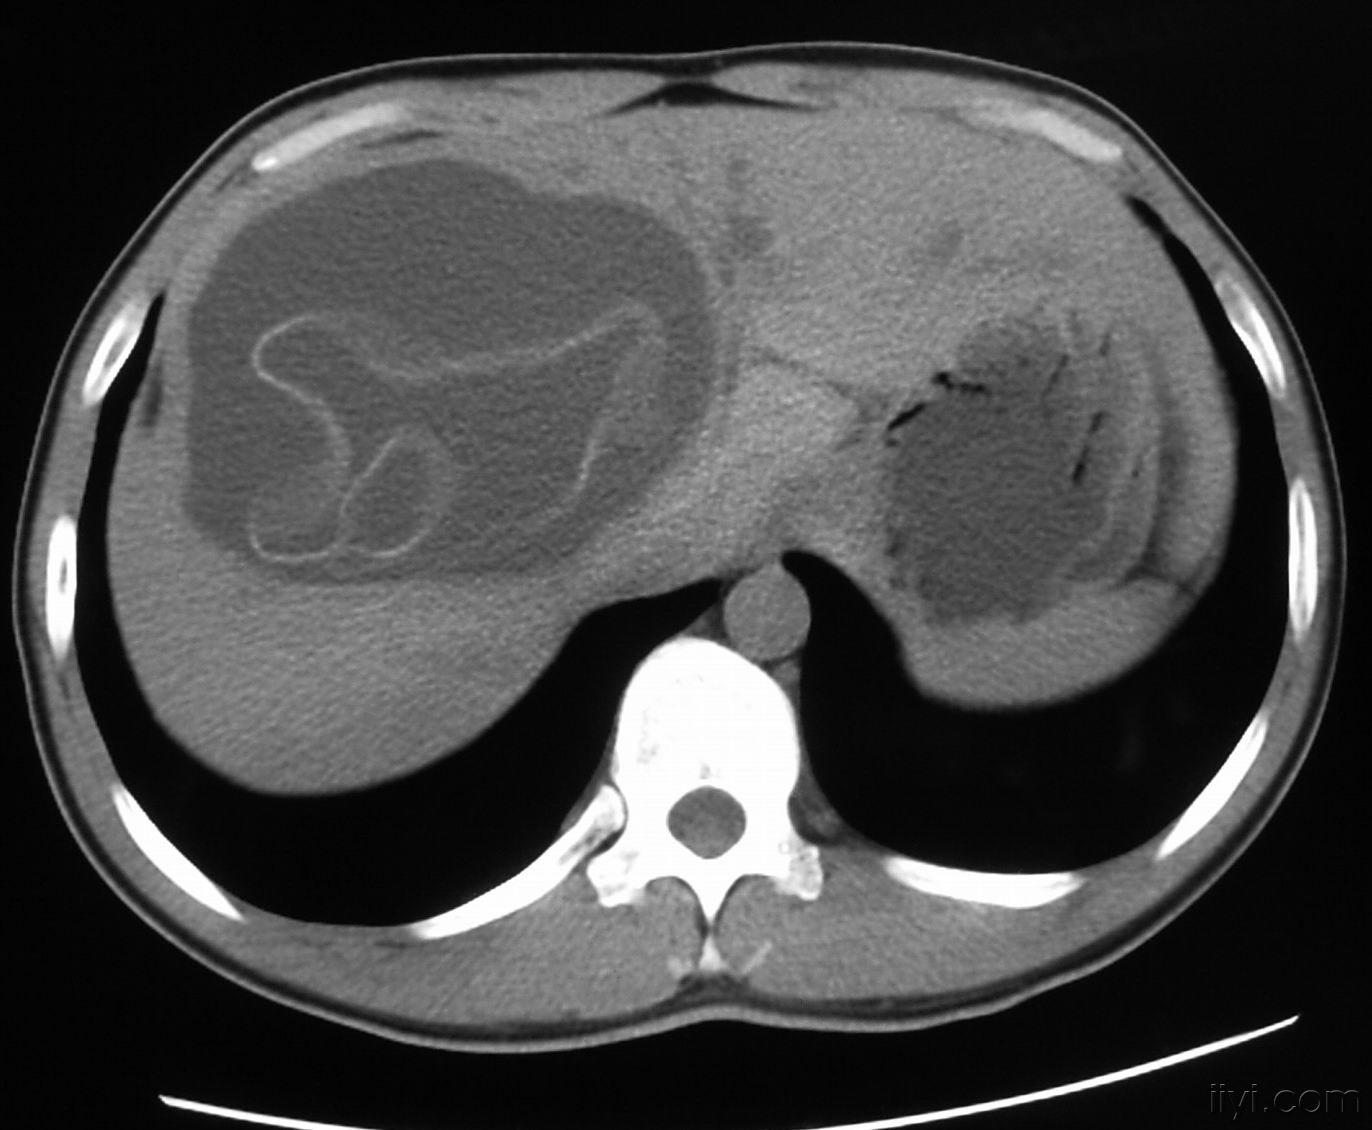

每日一例1212肝包虫病54岁男腹痛肝区不适